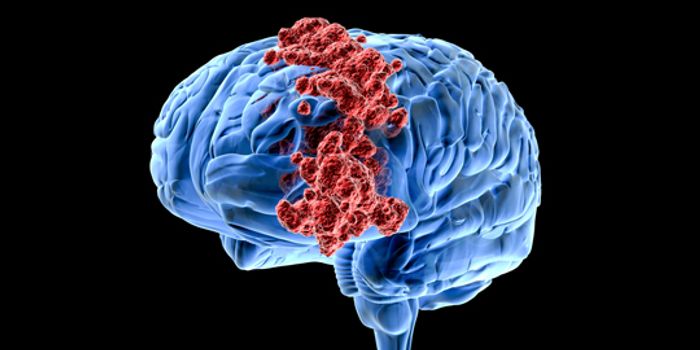

FEB 03, 2017CancerScientists on the quest to offer more hope for glioblastoma patients may have found a way to stop the growth of the dead ...

AUG 14, 2018NeuroscienceWhile neurological conditions such as Alzheimer's disease, ALS, Parkinson's and glioblastomas are frequently stu ...